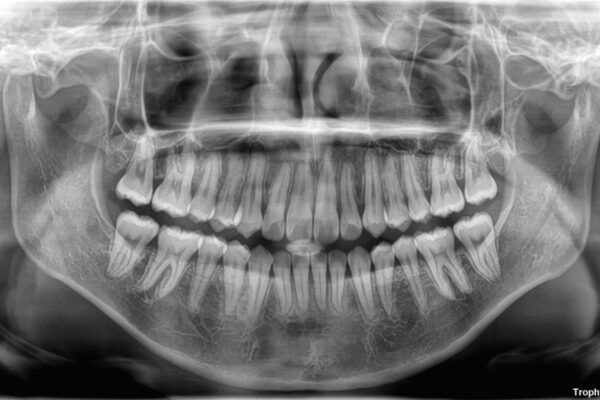

治療前

• 【モニター】前歯のデコボコをスッキリ解消!目立ちにくいワイヤー矯正でスピーディに治療完了 治療前画像

「前歯のデコボコ(叢生)をきれいに整えたい」とのことでご来院されました。